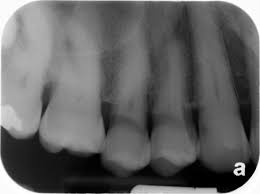

3. What condition can be detected in mesial surface of the tooth # 2.5?

10. What condition can be seen on the teeth # 1.5 and 1.4?

13. What condition can be seen on the teeth # 4.4 and 4.5?